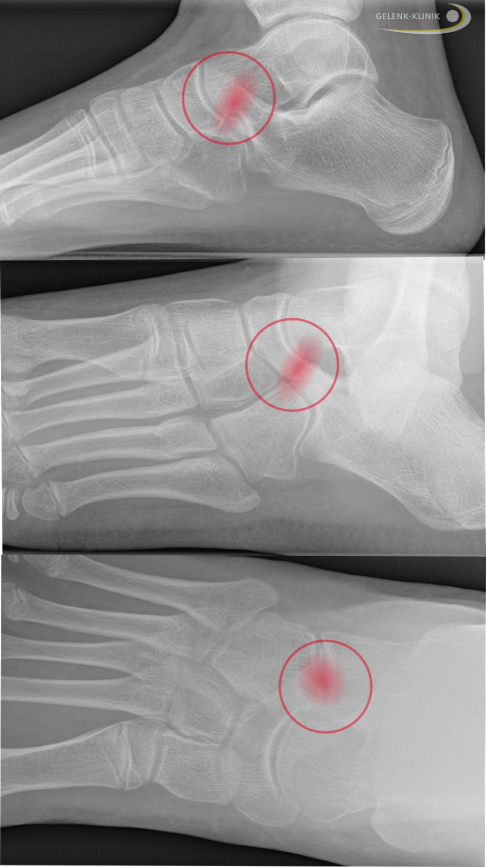

Röntgenbefund einer Coalitio calcaneonavicularis in 3 Ebenen (von der Seite, Schrägaufnahme, von oben). Man erkennt die bandförmige knöcherne Verbindung zwischen Fersenbein und Kahnbein (rot). © Gelenk-Klinik

Die erste Untersuchung erfolgt überwiegend durch eine Röntgenaufnahme des betroffenen Fußes in mehreren Ebenen. Der Fuß wird seitlich, von oben und in einem schrägen Winkel (45°) geröntgt.

Der Spezialist erkennt bei einer Coalitio calcaneonavicularis auf dem Röntgenbild die typische Verbindung zwischen dem vorderen Fersenbein und dem lateralen Kahnbeinanteil.

Bei Verdacht auf eine Coalitio talocalcanearis sucht der Fußspezialist nach dem sogenannten “C-Zeichen”: Die knöcherne Verbindung zwischen Sprungbein und Fersenbein erscheint im Röntgenbild wie ein auf dem Rücken liegendes "C".

Röntgenaufnahme einer Coalitio talocalcanearis: Die rote Linie markiert die Verknöcherung zwischen Talus und Calcaneus und bildet ein liegendes "C." © Gelenk-Klinik